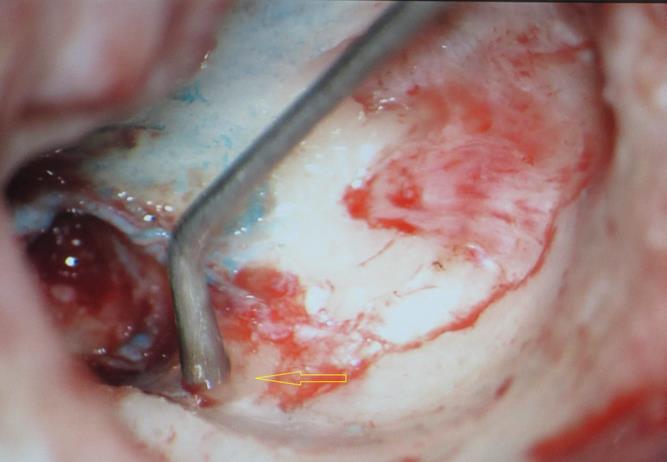

A 13 year old girl presented in ENT outpatient department with complains of recurrent right ear purulent discharge from pre and post auricular area for last 5 years. She had a history of incision and drainage in right post auricular area six months prior for similar complain. On local examination, there was right Grade II8microtia with atretic External Auditory Canal (EAC) and pre-auricular skin tag (Figure 1). A small fistulous opening was also seen in right cavum conchae region. Left ear examination was normal with intact tympanic membrane. Tuning fork tests using 256 and 512 Hz tuning forks showed moderate to severe conductive hearing loss in right ear with Rinne’s test positive in left ear. HRCT scan of temporal bones showed membranous atresia of right EAC with grade II microtia. Soft tissue density was seen filling the EAC and the entire middle ear cavity (Figure 2A). A CT based fistulogram done four months before our consultation identified multiple fistulous tracts situated in post auricular region and anterior to stylomastoid foramen in inframastoid region. These fistulous tracts were communicating through middle ear cavity (Figure 2B). There was associated erosion of posteroinferior and anteroinferior wall of EAC. Ossicles were dysplastic or eroded. Inner ear structures were normal. Patient underwent right radical mastoidectomy with wide conchal meatoplasty under general anaesthesia. Intraoperatively, there was right EAC membranous atresia with fistulous opening in cavum conchae. Cholesteatoma sac was seen filling the mastoid antrum area extending into middle ear cavity and EAC with erosion of posterior canal wall. Except remnant of malleus head which was fixed to epitympanic wall, no other ossicle was found. Oval window area showed bony depression without any overlying stapes footplate (Figure 3). Lateral semicircular canal bulge, facial nerve canal and chorda tympani were found at their usual locations (Figure 4). Obliteration of mastoid cavity posterior to vertical segment of bony facial canal was done using pedicled temporalis muscle flap to reduce the size of postoperative cavity. Middle ear cavity was covered with temporalis fascia graft.

Figure 3.Arrow pointing towards oval window area